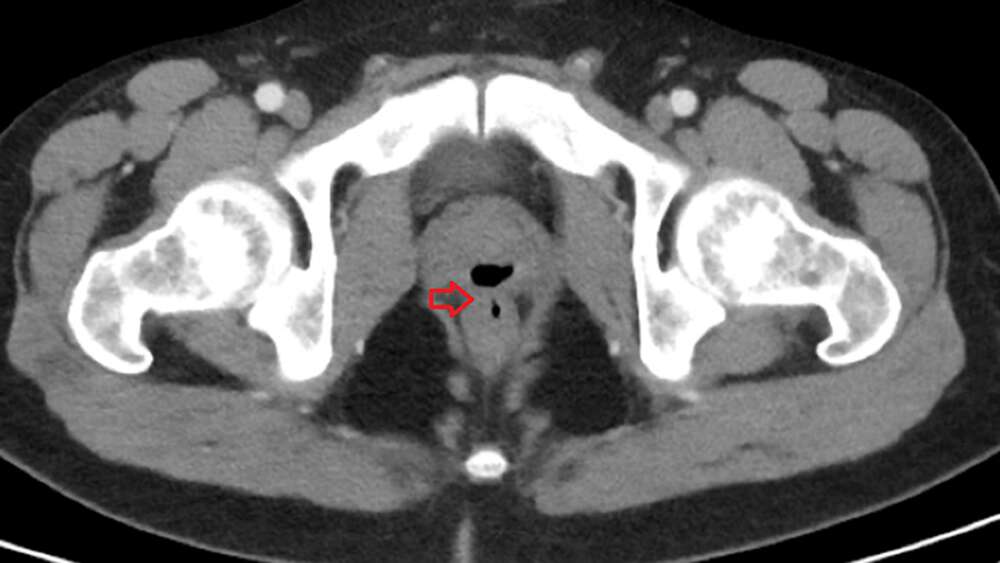

Un escáner reveló la causa de todos los problemas del paciente.

La radiografía mostró una «estructura llena de gas». Exámenes más específicos revelaron la presencia de una «fístula» (es decir un conducto interno anormal) entre el recto y la uretra, por donde se habían estado intercambiando diferentes fluídos.